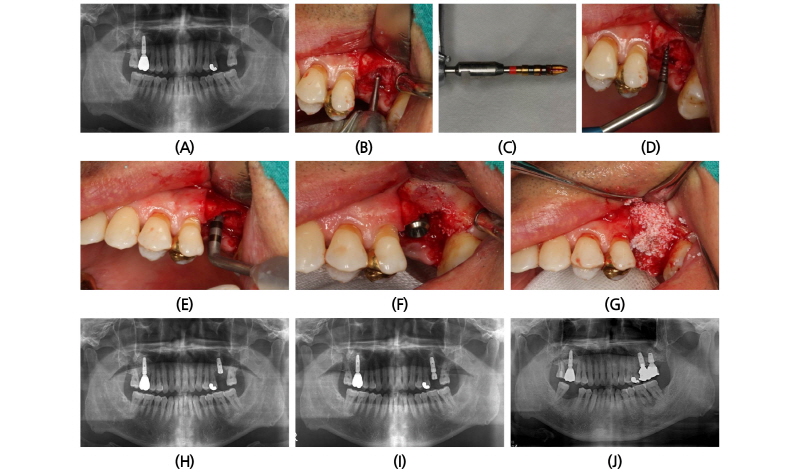

52세 남자 환자가 1년 전 상악 우측 제1소구치에 발치 후 즉시 임플란트를 식립하였으나 염증으로 제거하였고 이에 다시 임플란트 식립을 위해 내원하였다. 검진 결과 잔존 치조골의 높이는 약 7 mm 로 계측되었고 수평적 치조폭경이 협소하였다. 이에 상악동점막 거상술과 골이식을 동반한 임플란트 식립을 계획하였다. 치조정 접근을 통하여 골점막 피판을 거상시킨 후 Piezoelectric (Mectron, Carasco, Italy)을 이용한 drilling으로 상악동점막으로 접근하였고 이후 골이식재(Biocera)를 이식하였다. 직경 3.4 mm, 길이 10 mm으로 임플란트(Implantium, Dentium, Suwon, Korea)를 식립하였다. Buccal 쪽 치조골 소실이 심한 부위에 골이식을 추가로 진행하였다. Ostell mentor (Ostell AB, Sweden)을 이용한 ISQ 값은 55였다. 치유지대주를 체결하여 4-0 Vicryl (Johnson & Johnson, PA, USA)로 봉합하였다. 식립 다음날 시술 부위 소독을 하였다. 식립 10일 후 봉합사를 제거하였다. 식립 5개월 후 최종 보철물을 수복하였고 식립 1년 7개월 후 파노라마 방사선 사진(2011.02.21)에서 임플란트가 정상적으로 유지되고 있다(Fig. 6).